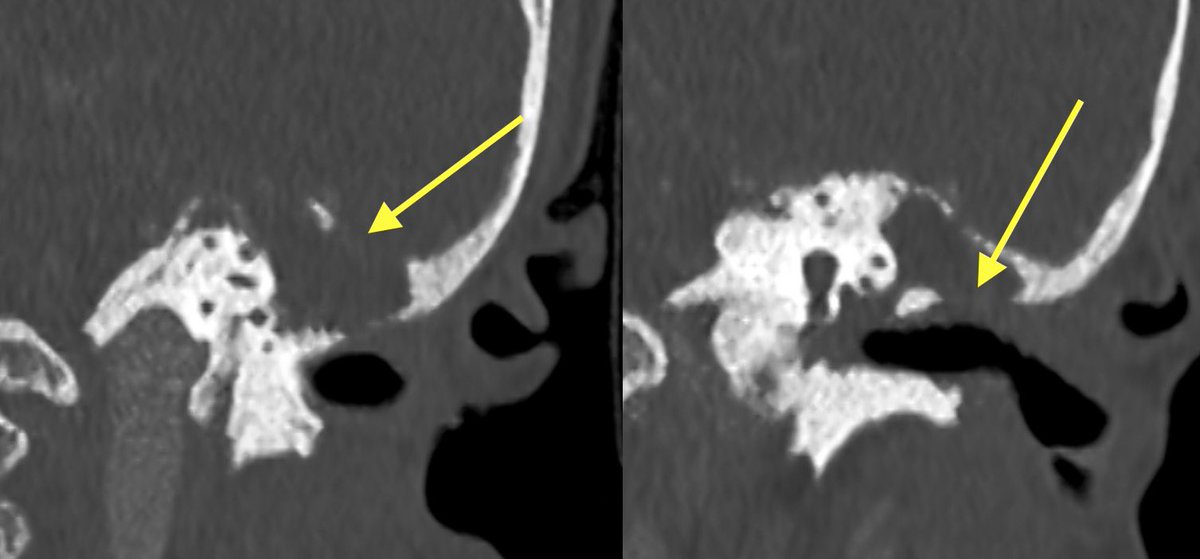

Initial T bone CT:

▶️Coalescence of mastoid air cells

▶️diffuse dehiscence of Tegmen tympani

▶️Middle ear ossicle erosions

▶️dehiscence of the roof of the EAC

▶️dehiscence of semicircular canals and tympanic segment of facial nerve

💡 make sure to report all areas of dehiscence as it can affect surgical approach